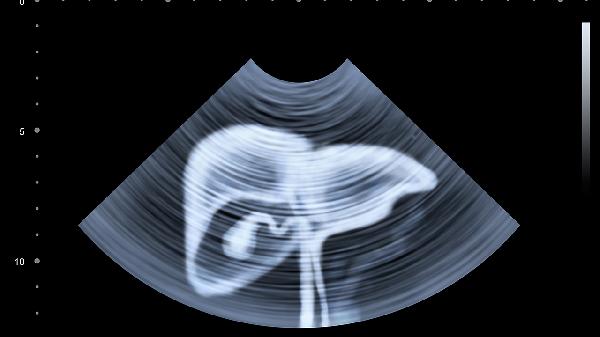

通过肝功能检查、超声等动态评估恢复情况。胆红素、转氨酶水平变化反映肝细胞修复状态,凝血功能监测合成能力。每1-3个月复查直至指标稳定,持续异常需调整治疗方案。